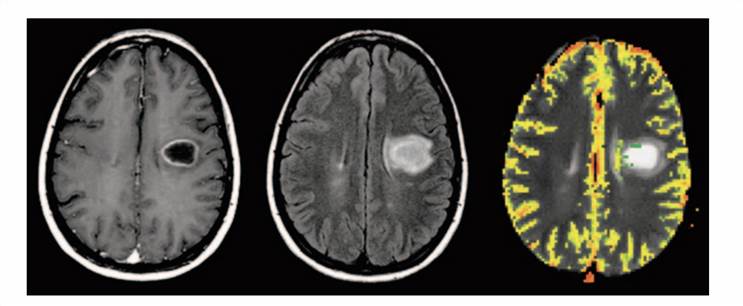

Dynamic Contrast-Enhanced Magnetic Resonance Imaging of Brain Tumor. Fig.2 Dynamic Contrast-Enhanced Magnetic Resonance Imaging of Brain Tumor.2

Contrast-Enhanced MRI Tumor Imaging Service

Our unique MRI analysis system can map the structure inside cancer tissue. MRI has the unique advantages of high resolution on the micron scale, no ionizing radiation damage, high soft tissue resolution, and no need to use contrast agents to show the structure of blood vessels. To date, our MRI system can be a powerful and versatile tumor imaging system, especially in vascular carcinomas.